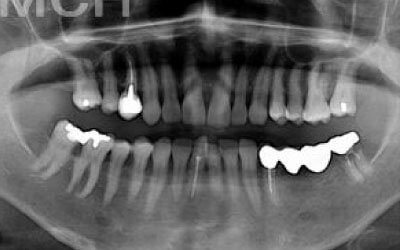

歯が抜けたままにしたら他の歯がズレてしまいました。どうしたらよいでしょう?

軽度のズレなら調整や詰め物で対応可能ですが、大きく傾いた場合は矯正や被せ物が必要です。ズレが広がる前に早めの診査・治療をおすすめします。

ただインプラントは、人工歯根を通して骨が力を支えるので、残っている歯への負担が圧倒的に少ないのです。

ブリッジなどの治療では前後の歯を大きく削る必要があります。場合によっては、虫歯でもないのに歯の神経をとることも。実は神経をとって被せ物をすると、歯は一気に最終ステージになってしまいます。

しかしインプラント治療なら、前後の歯を削る必要も神経をとる必要もありません。歯の寿命を延ばす上でも、健康な歯をできるだけ削らないのはとても大切なことなのです。